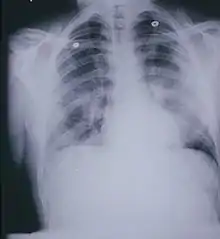

.jpg.webp)

على الرغم من أن كل من الأعراض وموجودات التصوير موصوفة جيداً، إلا أنها غير نوعية ولا يمكن تمييزها عن العديد من الحالات الأخرى. على سبيل المثال، قد تظهر صورة الصدر البسيطة عتامة سنخية، وقد يظهر التصوير الطبقي المحوسب مظهر "الحجارة المرصوفة"، وكلاهما يظهر بشكل شائع في العديد من الحالات الأخرى.[26] وبالتالي، فإن التشخيص يعتمد في المقام الأول على موجودات التشريح المرضي.